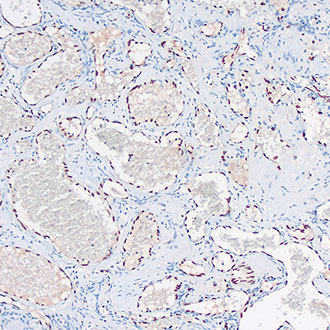

CD34

CD34 -